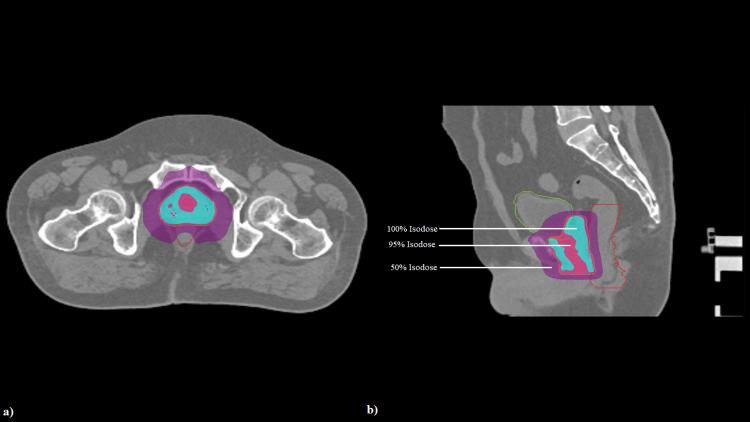

Prostate cancer, when detected early, can be either actively observed or treated radically based on clinical, pathological, and imaging features. Radical treatment options include radical prostatectomy, radical radiation as external beam radiotherapy (EBRT), or brachytherapy. EBRT for prostate cancer can be given in different ways. It may be delivered in smaller doses over several weeks, known as conventionally fractionated radiation therapy (CF-RT), or in larger doses over fewer sessions, as in moderately hypofractionated radiotherapy and ultra hypofractionated radiotherapy, also known as stereotactic body radiation therapy (SBRT). Recent studies have shown that SBRT is non-inferior to CF-RT, and the National Comprehensive Cancer Network guidelines also suggest SBRT as a treatment option for localized disease. As SBRT uses a high dose per fraction for treatment, it requires a very tight margin around the planning target volume and intrafractional motion management to prevent the organs at risk from receiving a high dose and subsequent toxicities developing from it. In this case series, we report our clinical experience with prostate SBRT using the Radixact® X9 (Accuray, Sunnyvale, CA, United States) tomotherapy machine with Synchrony® fiducial tracking for real-time motion tracking and correction.

前列腺癌若早期发现,可根据临床、病理及影像特征进行积极观察或根治性治疗。根治性治疗方案包括根治性前列腺切除术、作为外照射放疗(EBRT)的根治性放疗或近距离放疗。前列腺癌的EBRT可采用不同方式给予。它可以在数周内以较小剂量给予,即传统分割放疗(CF-RT),或者在较少疗程内以较大剂量给予,如在中等程度的低分割放疗和超分割放疗中,也称为立体定向体部放疗(SBRT)。最近的研究表明,SBRT不劣于CF-RT,美国国立综合癌症网络指南也建议将SBRT作为局限性疾病的一种治疗选择。由于SBRT每次分割使用高剂量进行治疗,它需要在计划靶区周围有非常精确的边界以及进行分次内运动管理,以防止危及器官接受高剂量并由此产生后续毒性。在本病例系列中,我们报告了使用Radixact® X9(美国加利福尼亚州桑尼维尔市的Accuray公司生产)断层放疗机及Synchrony®基准跟踪技术进行实时运动跟踪和校正的前列腺SBRT临床经验。